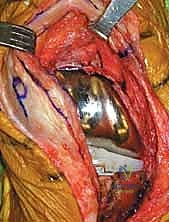

الخطوة الثانية: الفتح الجراحي المتقدم (Extensile Exposure)

الركبة المتصلبة تكون قاسية جداً ويصعب كشفها بالطرق العادية. يستخدم الدكتور هطيف تقنيات جراحية دقيقة لحماية الوتر الرضفي من التمزق، وقد يتطلب الأمر إجراء قص عظمي بسيط في نتوء الساق (Tibial Tubercle Osteotomy) أو قص في وتر العضلة الرباعية (Quad Snip) للوصول الآمن للمفصل.

الخطوة الثالثة: الاستئصال الجذري للأنسجة الندبية (Radical Synovectomy)

يتم إزالة كافة الأنسجة المتليفة والندبية الكثيفة (Scar tissue) التي تكونت في الجيوب المفصلية وخلف الركبة. هذه الخطوة وحدها كفيلة بتحرير جزء كبير من حركة المفصل.